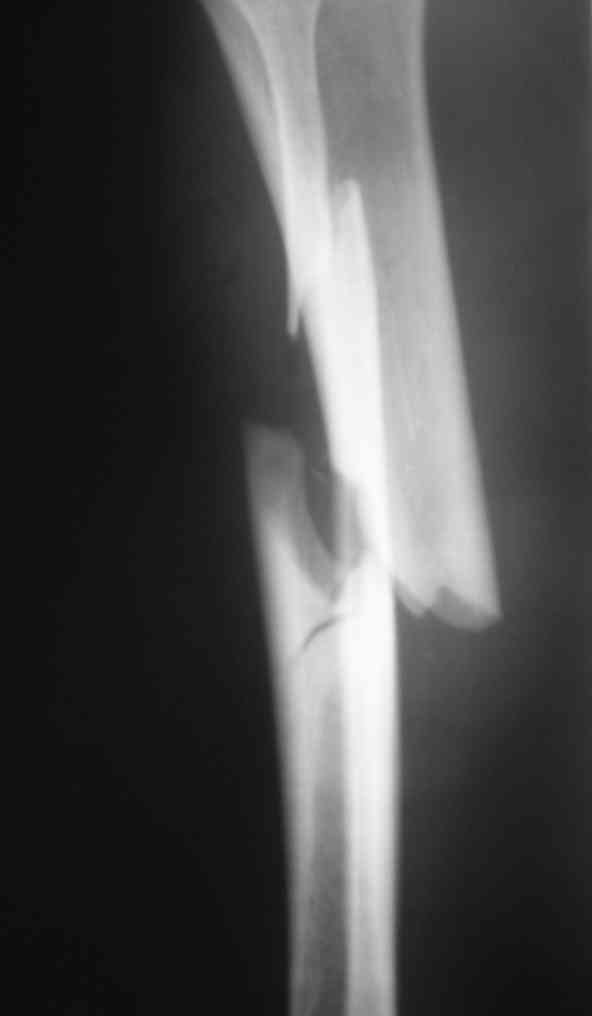

Дорогой Александр. Имею скромный опыт использования системы Fixion при

переломах плеча, бедра и тибии. Всего 18 наблюдений с сентября 2007

г.Результаты отличные. Гвоздь индивидуален для каждого медулярного

канала. Легко имплантируется как в узкий, так и в деформированный

канал. Это позволяет применять метод интрамедулярного остеосинтеза без

ненужных потерь времени операции, флюороскопии и реально снижает

крвопотерю и операционный риск. Удаление происходит без проблем.

Особенно интересны больные с ипсилатеральными переломами бедра и голени.

В отношении ранней нагрузки при спиральных переломах лучше не

торопиться. По данному случаю необходимо достигнуть исчезновения щели

между штифтом и внутреним кортексом по Rg. А так картинка прекрасная -

и длина сегмента и репозиция. Можно поздравить, коллега!